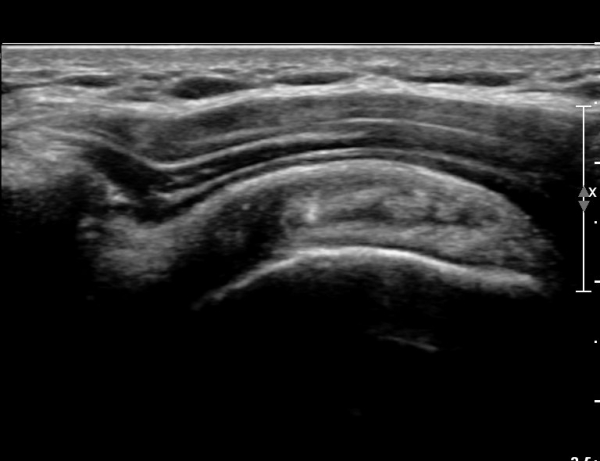

ÃÊÀ½ÆÄ ¼Ò°ß :  ȸÀü±Ù°³ °í¶û  °Ë»ç¸¦ À§ÇÑ »ó¿Ï Á߸³À§¿¡¼­ °ß°©ÇÏ±Ù°Ç °Ë»ç¸¦ À§ÇØ  ŽÃËÀÚ¸¦

¾à°£ ³»ÃøÀ¸·Î ±â¿ï¿© ½ÃÇàÇÑ °ß°©ÇÏ±Ù°Ç Á¾´Ü¸é°Ë»ç¿¡¼­ °ß°©ÇÏ±Ù°Ç »óºÎ°ÇÀÇ

Á¾¹æÇ⠺и®(½ÇÁú³» ÆÄ¿­)°¡ °üÂûµÈ´Ù(»çÁø 1).

ŽÃËÀÚ¸¦ Á¶±Ý ´õ ¸»´Ü¹æÇâ(caudal)À¸·Î À̵¿ÇÏ´Ï ÆÄ¿­ÀÌ ´õ¿í ¶Ñ·ÈÇÏ´Ù(»çÁø 2, 3).